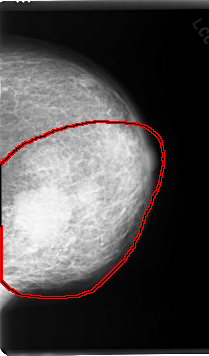

C_0055_1.LEFT_MLO

FILE: C_0055_1.LEFT_MLO.OVERLAY

TOTAL_ABNORMALITIES 1

ABNORMALITY 1

LESION_TYPE CALCIFICATION TYPE PLEOMORPHIC DISTRIBUTION SEGMENTAL

ASSESSMENT 5

SUBTLETY 5

PATHOLOGY MALIGNANT

TOTAL_OUTLINES 1

BOUNDARY